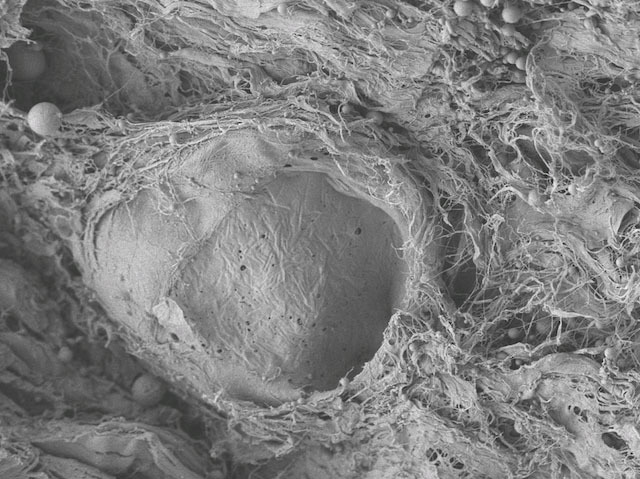

When someone gets an organ transplant, there’s a risk that their immune system will attack it, as it doesn’t have the same cellular markers as the rest of their body. Lately we’ve been able to reduce this risk for certain organs by decellularising them – stripping the cells away to leave the supportive structural mesh called the extracellular matrix (ECM) – and growing the patient’s own cells on them. Scientists recently examined how decellularisation affects the ECM in different tissues, using samples from pigs. They found that up close there were small structural changes in the ECMs. Additionally, muscular tissues could take more stress after decellularisation, but skin became weaker. The image shows decellularised skin: the hole used to contain a hair follicle, but these cells have been extracted: removing cells like this partly contributed to weakening the skin. This research helps us develop better ways to treat transplant tissue.